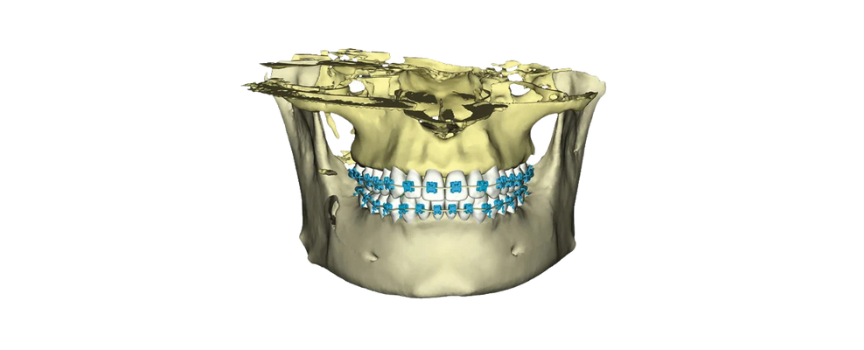

Idealny do obrazowania aparatów ortodontycznych

Planmeca ProMax 3D Mid posiada również certyfikat pozwalający na stosowanie protokołu leczenia SureSmile. Protokół obrazowania aparatów ortodontycznych doskonale sprawdza się w obrazowaniu pacjentów z aparatami ortodontycznymi.

Obrazy Kliniczne Planmeca ProMax 3D Mid